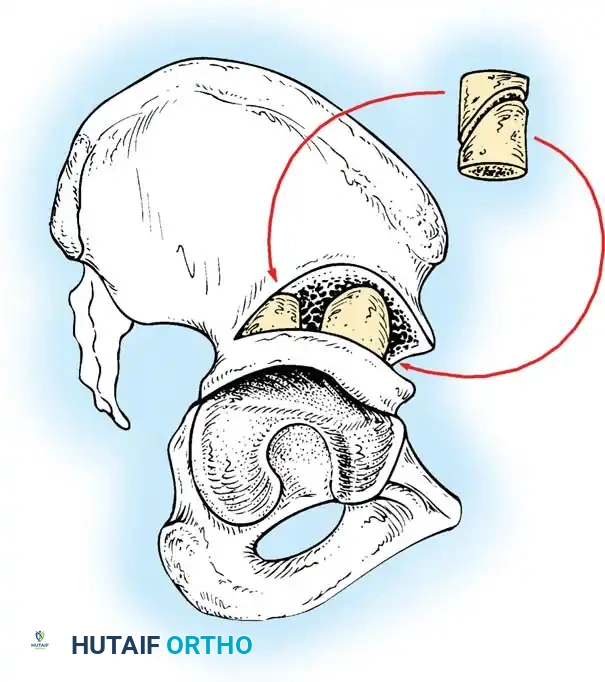

- Salter Innominate Osteotomy:

- Indications: Children aged 18 months to 6 years with a congruous joint but anterolateral acetabular deficiency.

- Biomechanics: A complete transverse cut is made through the ilium just above the acetabulum to the sciatic notch. The entire acetabulum is rotated anteriorly and laterally, hinging on the pubic symphysis.

- Fixation: A triangular bone graft (harvested from the iliac crest) is placed in the osteotomy site, and the construct is stabilized with threaded Kirschner wires.

Diagrammatic representation of the Salter Innominate Osteotomy. Note the complete iliac cut and the placement of the triangular bone graft to redirect the acetabulum.

- Pemberton Pericapsular Osteotomy:

- Indications: Severe dysplasia with a capacious acetabulum.

- Biomechanics: An incomplete cut is made through the ilium, curving down to the triradiate cartilage, which acts as a hinge. This reshapes the acetabular roof, reducing its volume and improving anterolateral coverage.